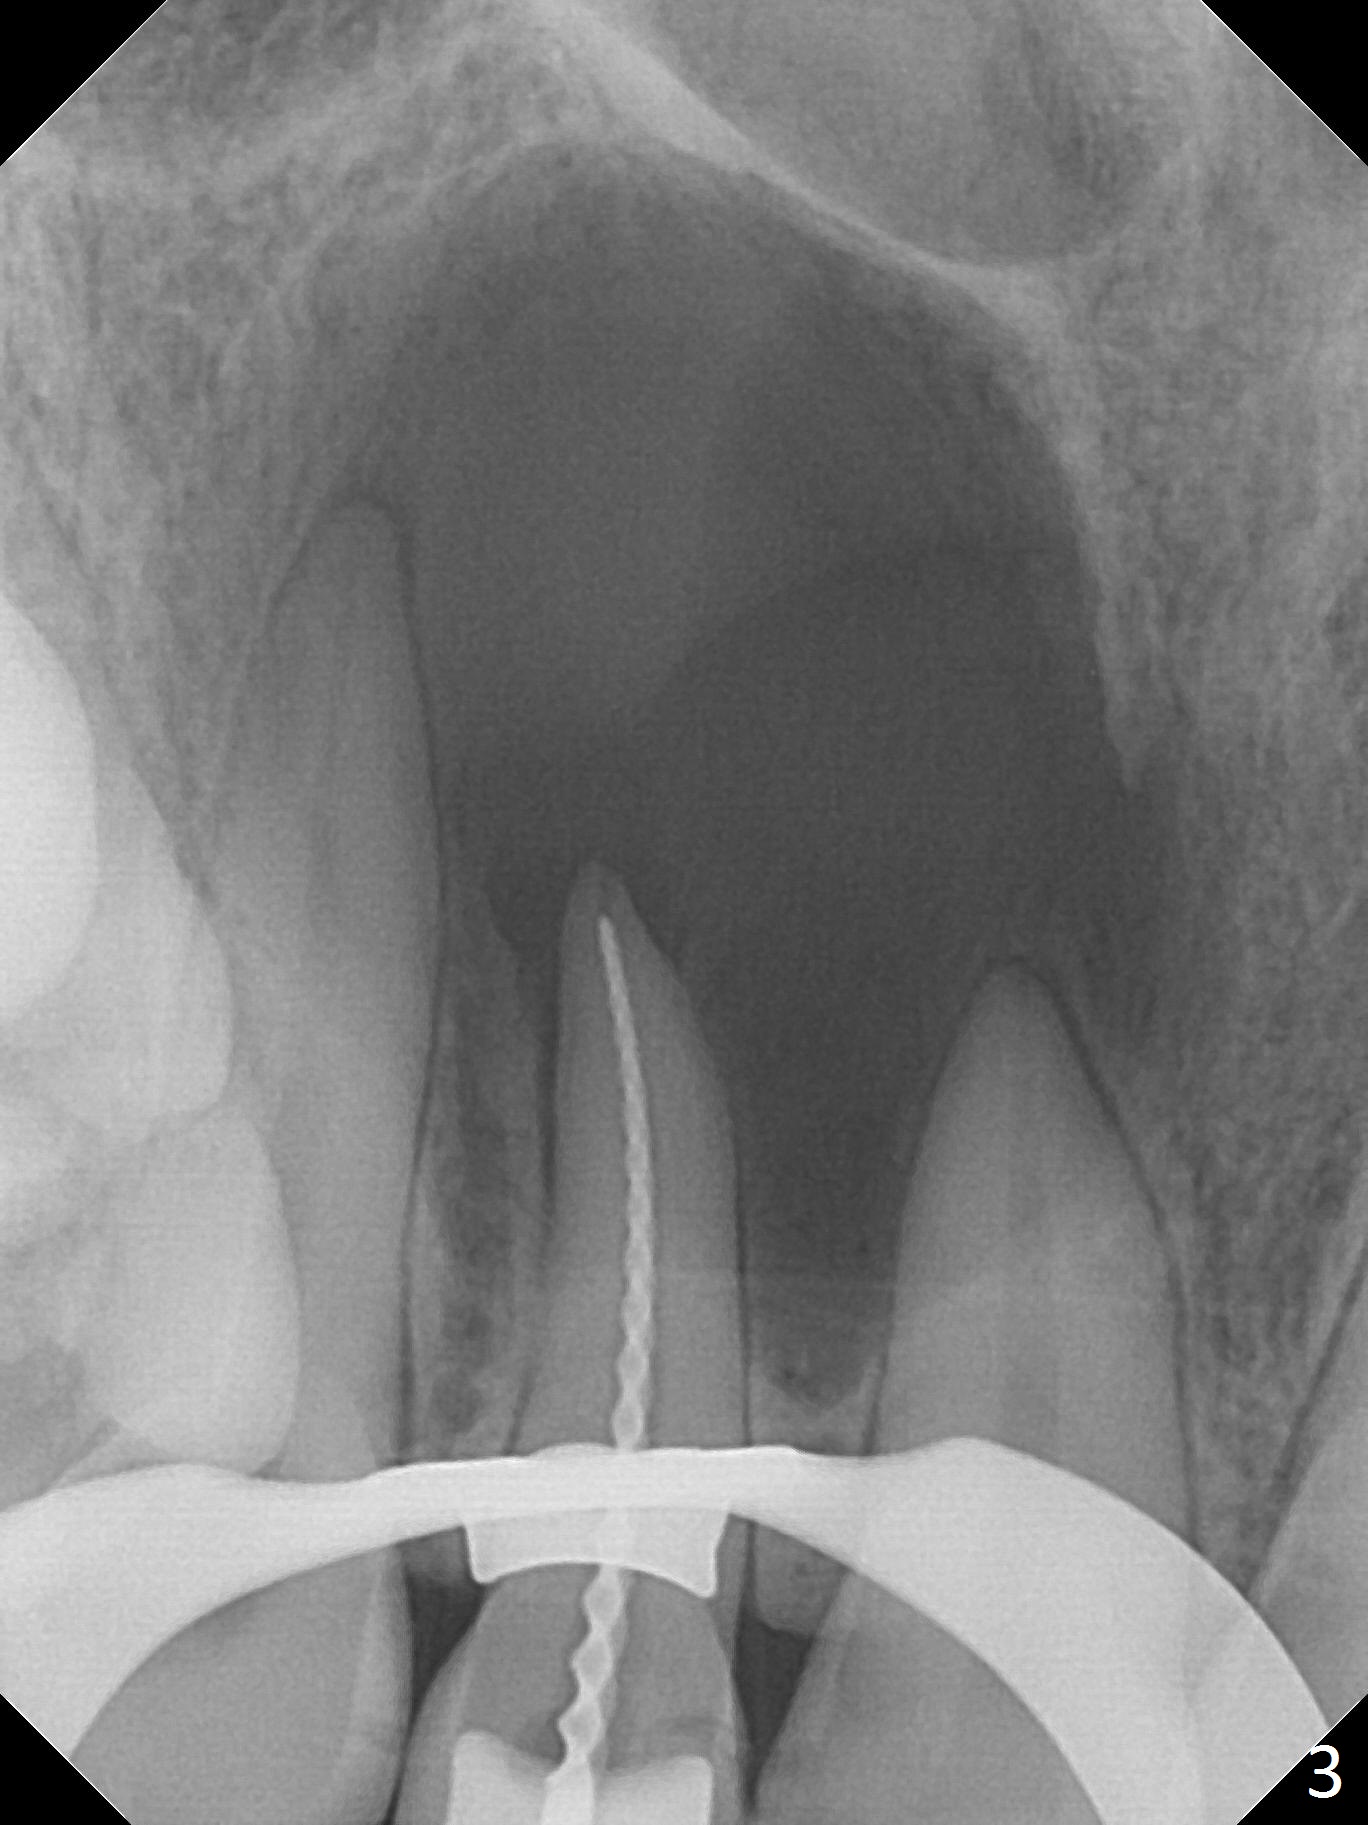

A 30-year-old woman presents to clinic with a large palatal swelling (Fig.1,2). In fact the tooth #7 is necrotic with a periapical radiolucency (Fig.2 arrowheads). RCT is initiated; note the curved canal and file (Fig.3). To reduce the large lesion, Calcium Hydroxide paste is placed in the enlarged canal (Fig.4 *). In a month, the palatal lesion decreases (Fig.5). After re-debridement of the canal, Calcium Hydroxide paste is re-applied.